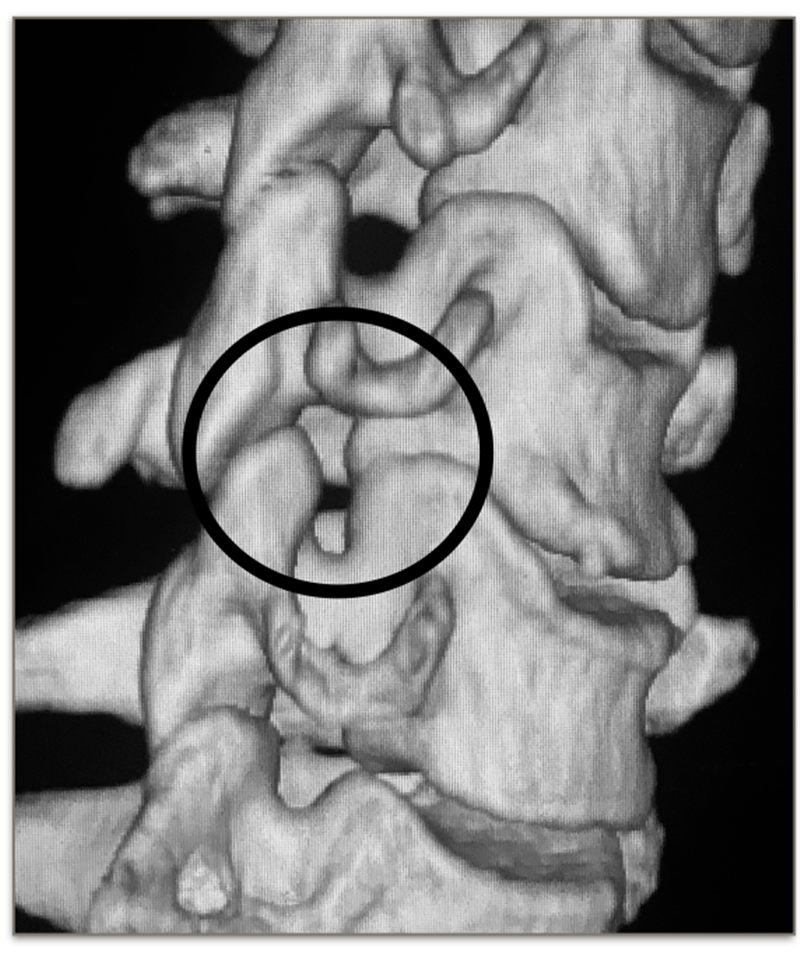

增生的钩椎关节

Orofinod等人发现,在成人颈椎中,原本存在于钩突与上位椎体间的疏松纤维组织、血管被纤维软骨及新生骨组织所代替。这一改变使得钩突被认为是随着年龄的增长而出现的一种退变现象。在颈椎退变过程中,由髓核脱水、椎间盘高度丢失等因素导致钩突与上一位椎体直接接触面积增大或承载压力变大,因而在钩突周围出现骨赘。